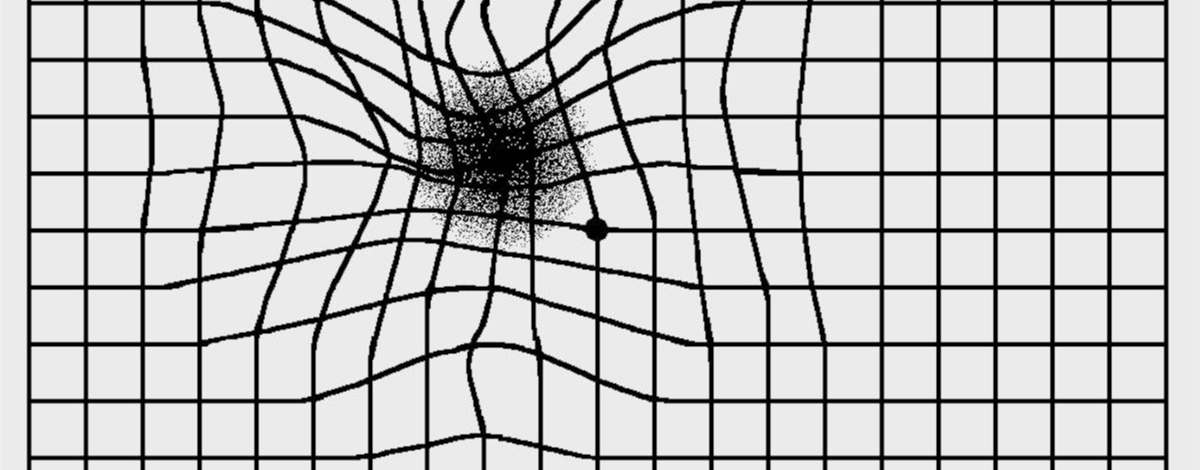

I sintomi più frequenti sono la diminuzione della vista, la visione offuscata o la deformazione delle immagini.

Le linee appaiono distorte e i numeri e le lettere possono saltare di rigo.